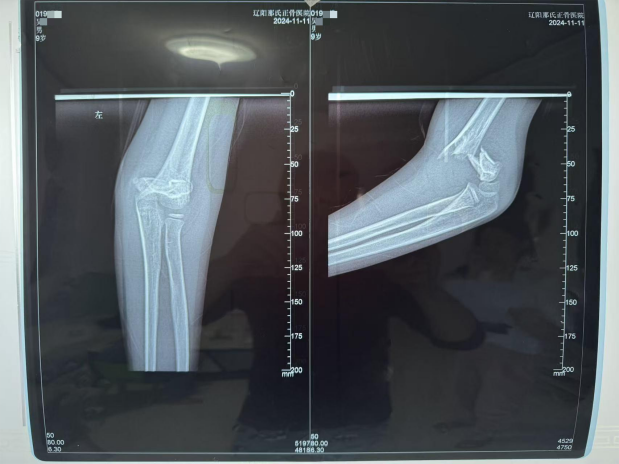

据受伤儿童家长反映,2024年11月11日,三年级学生吴某在辽阳市白塔区卫国路金某果托管班操场玩耍时,遭遇多次伤害。当时,同校五年级学生杨某某从滑梯滑下,直接撞倒站在滑梯下方的吴某,致其倒地。随后,吴某又遭到三名同学倒压与拖拽,导致左臂受伤。事发过程中,吴某多次呼救,但托管班工作人员仅短暂观望后便离开,未及时上前查看或询问伤情。最终,吴某由同学扶起,自行去找托管班老师说明情况,才被安排送往医院。家长表示,事发后托管班未第一时间通知家长,施救过程中未拨打120急救电话,也未将吴某送往最近的急救中心,而是送至距离托管班约10公里的一所骨伤医院,家长认为此举直接影响了对孩子的及时救治。经医院诊断,吴某为左侧肱骨远端骨折,接受手术治疗。

伤情报告,(家长提供)

因武圣镇相关部门未同意家长的伤情鉴定请求,吴某家长于2025年9月提起民事诉讼。2026 年1月,经辽阳市中级人民法院委托,司法鉴定机构出具鉴定意见:该学生左肱骨损伤构成十级伤残。

伤情鉴定,(家长提供)